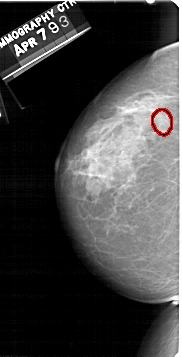

A_1512_1.LEFT_CC

LEFT_CC LINES 5341 PIXELS_PER_LINE 2716 BITS_PER_PIXEL 12 RESOLUTION 43.5 OVERLAY

FILE: A_1512_1.LEFT_CC.OVERLAY

TOTAL_ABNORMALITIES 1

ABNORMALITY 1

LESION_TYPE MASS SHAPE OVAL MARGINS CIRCUMSCRIBED

ASSESSMENT 3

SUBTLETY 4

PATHOLOGY BENIGN

TOTAL_OUTLINES 1